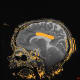

MRI with heat map overlay shows laser ablation of the main body of the corpus callosum. Credit: Angela V. Price, M.D.

In recent years, Price and a few other pediatric neurosurgeons across the country have started performing a minimally invasive procedure, in which a tiny laser is inserted through a small incision in the skull to burn away a portion of the corpus callosum, a band of tissue that connects the left and right hemispheres of the brain. The traditional operation involves a large incision to remove a portion of the skull for access. Price and colleagues reviewed 19 patients who underwent 24 procedures: 16 had gone through open corpus callosotomies, and eight underwent laser procedures.

Results showed that for both types of procedures, drop seizures were practically eliminated, and rates of post-surgical complications were low. But the laser technique required a patient to spend less than half the time in the pediatric ICU and decreased the overall length of stay in the hospital (4.6 days versus 5.7 days). In addition, children required no inpatient rehabilitation compared with about 20 percent of those receiving open repair, and lost 12 times less blood (7 milliliters versus 84 milliliters).

Price notes that the operating time for laser procedures was nearly double that of the open procedure group (492 minutes versus 249 minutes), partially due to MRI imaging before and during the operation. The laser patients also took corticosteroid drugs about three times longer than those who had open procedures.